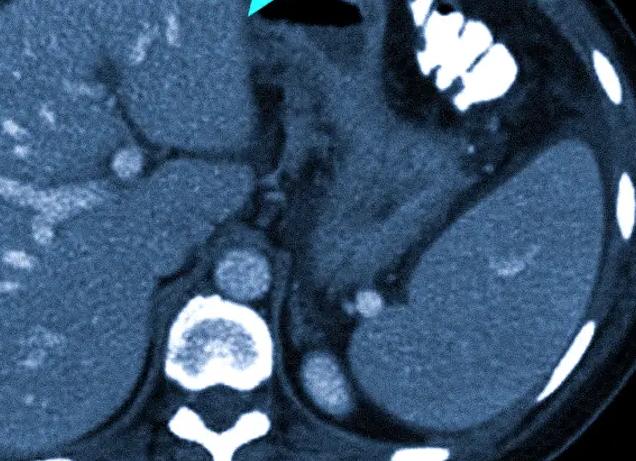

Получая у врача назначение на обследование такого важного органа как головной мозг, пациент задумывается – какой вид диагностики выбрать? Среди самых современных методик диагностирования наиболее информативными считаются компьютерная томография и магнитно—резонансная томография. Так КТ или МРТ головного мозга — какая методика эффективнее, что лучше?